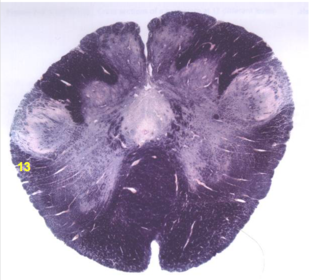

| Nucleus gracilis | |

| Accessory nucleus | |

| Medial longitudinal faciculus | |

| Pyramidal decussation | |

| Medullary pyramids | |

| Anterior spinocerebellar tract | |

| ALS | |

| Posterior spinocerebellar tract | |

| Spinal tract of V | |

| Spinal nucleus of V | |

| Nucleus cuneatus | |

| Fasciculus cuneatus | |

| Fasciculus gracilis | |

| Central canal | |